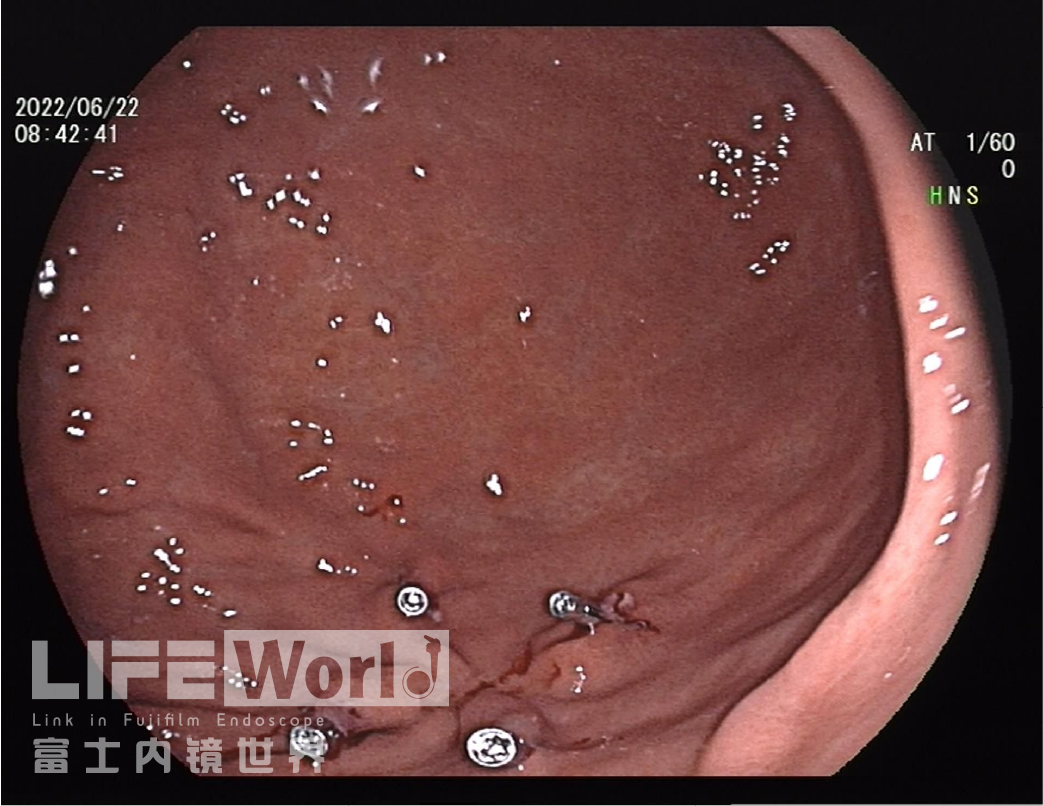

慢性萎缩性胃炎(C-2):胃窦、胃角及胃体下段小弯侧黏膜变薄,凸凹不平。Hp现症感染:胃体黏膜肿胀,弥漫性发红。

白光观察:胃体下段大弯侧可见一处中央凹陷的病变,色红,范围约1.2×0.6cm,周围黏膜集中、中断。